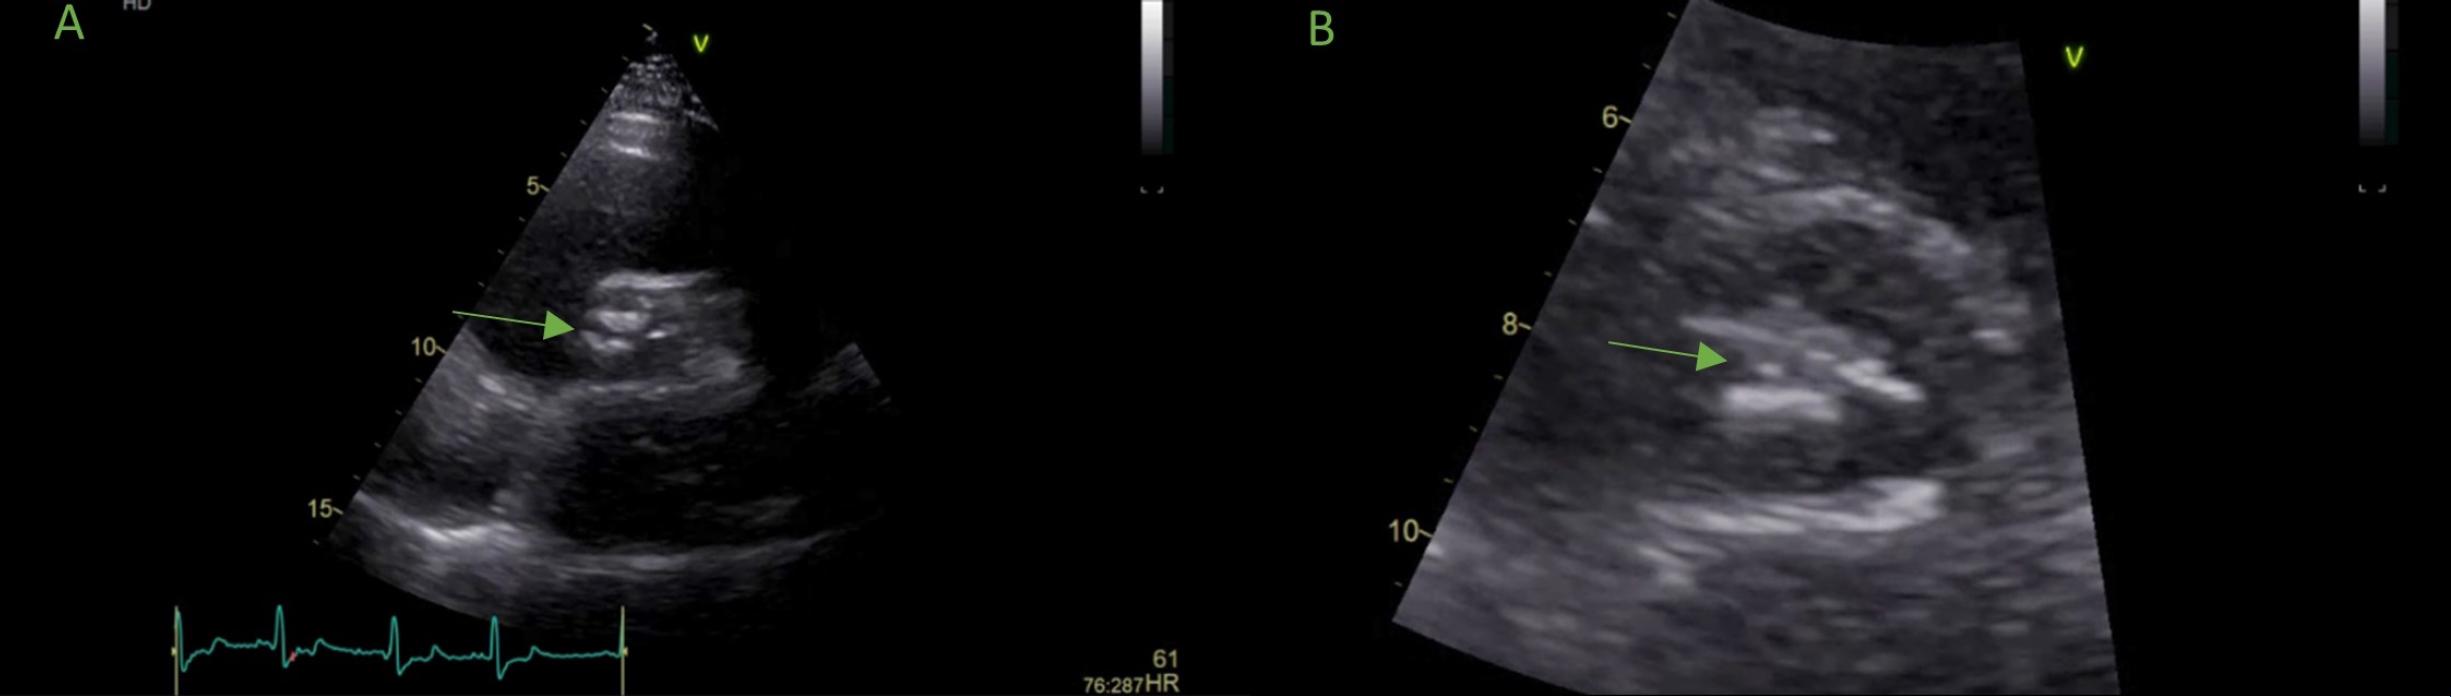

Initial (A) transthoracic echocardiography in short axis view showing calcified aortic valves and repeated (B) echocardiography with suspicion of a small mass attached to the aortic cusp.The arrows indicate (A) a degenerative tricuspid aortic valve and (B) a small mass attached to the aortic valve.